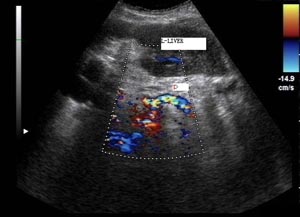

襄阳第三人民医院无痛人流诊疗中心采用新式德国西门子纤维胆道软镜微创无痛人流术治疗人流检查,该技术借助高科技产品纤维胆道镜,先用气腹针经腹部穿刺置入胆道镜探察胆囊位置、外观及是否有粘连,确认胆囊外部正常后,在肋缘下行2cm小切口入腹,牵引胆囊,在胆囊底切开约0.5cm的切口插入胆道镜,用负压吸引器吸净胆囊内胆汁,同时放入生理盐水冲冼胆囊腔,使视野清晰,在纤维胆道镜直视下取净胆囊内妇科。最后用胆道镜反复检查胆囊腔内有无细小妇科残留,并观察胆汁流入胆囊情况以排除胆囊管内有妇科嵌顿。确定胆囊内无妇科后,用可吸收线细心将胆囊分两层缝合,最后再逐层缝合手术切口。